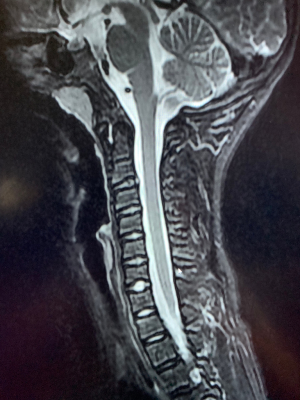

Case 3 (Figures 8 and 9 )

A 65-year-old male without significant past medical history presented to the outpatient department with a chief complaint of difficulty walking for more than 10 months’ duration, and neck and shoulder pain for 40 years. Physical examination showed bilateral upper extremity hyperreflexia, bilateral Babinski reflex, a positive Hoffman’s test, and a decrease in multidermatomal upper extremity sensation during pinprick testing. Furthermore, decreased grip strength and compromised coordination was noted, evidenced by altered gait pattern. Radiographic examination of the cervical spine showed a loss of activity in the PAOI on X-ray (ratio of PAOI = ~0.6). The MRI demonstrated the presence of severe spinal compression in C4/5. The patient elected to undergo cervical surgical treatment.